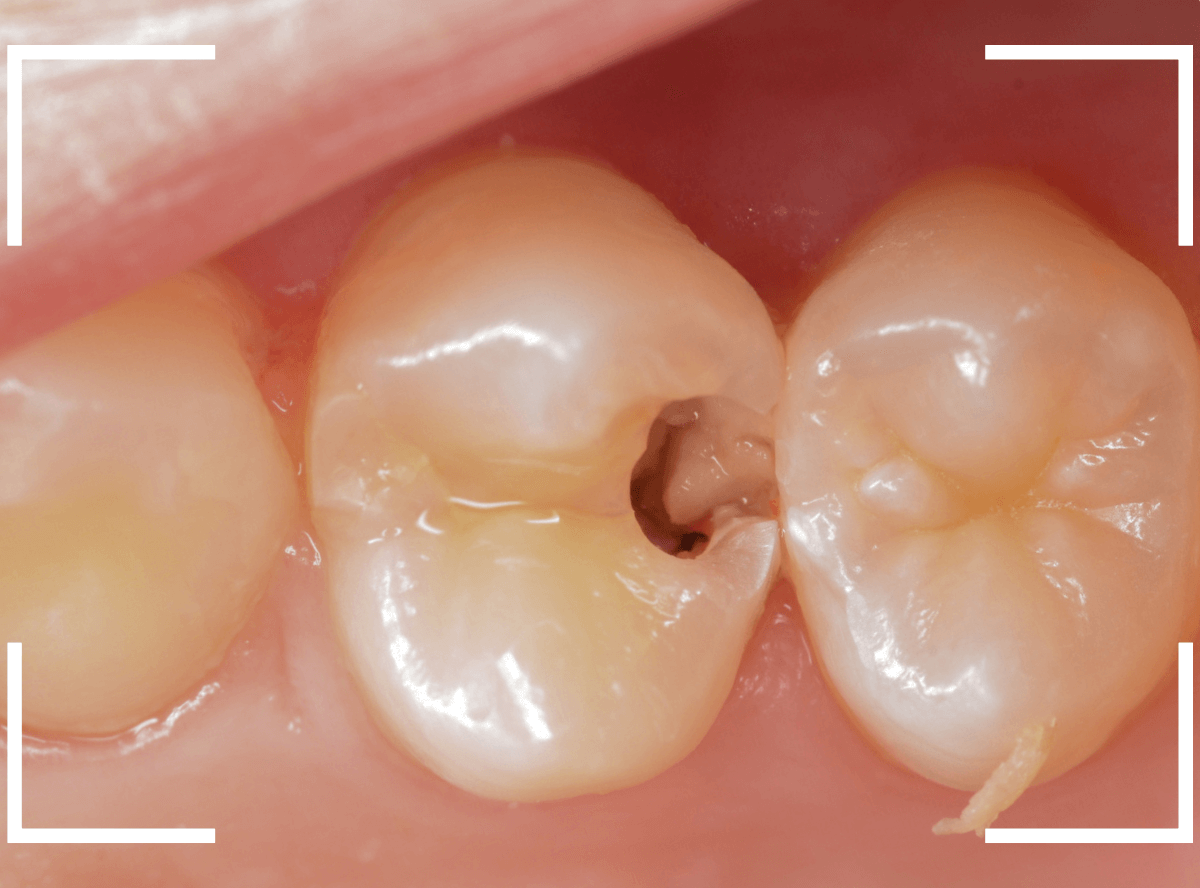

上の奥歯の虫歯が見つかった患者さんです。

初診のチェックの際に、上から目視すると、レジンがつめてある〇部分が薄暗く黒くなっているので、これは虫歯があるな、とわかりました。

レントゲン写真で確認します。

赤いラインが虫歯と思われる部分、青いラインが歯の神経です。

先ほどの〇部分は明らかな虫歯になっているのがわかります。

この辺りはレジンがつめてありますが、その下もうっすらと虫歯になっていそうです。